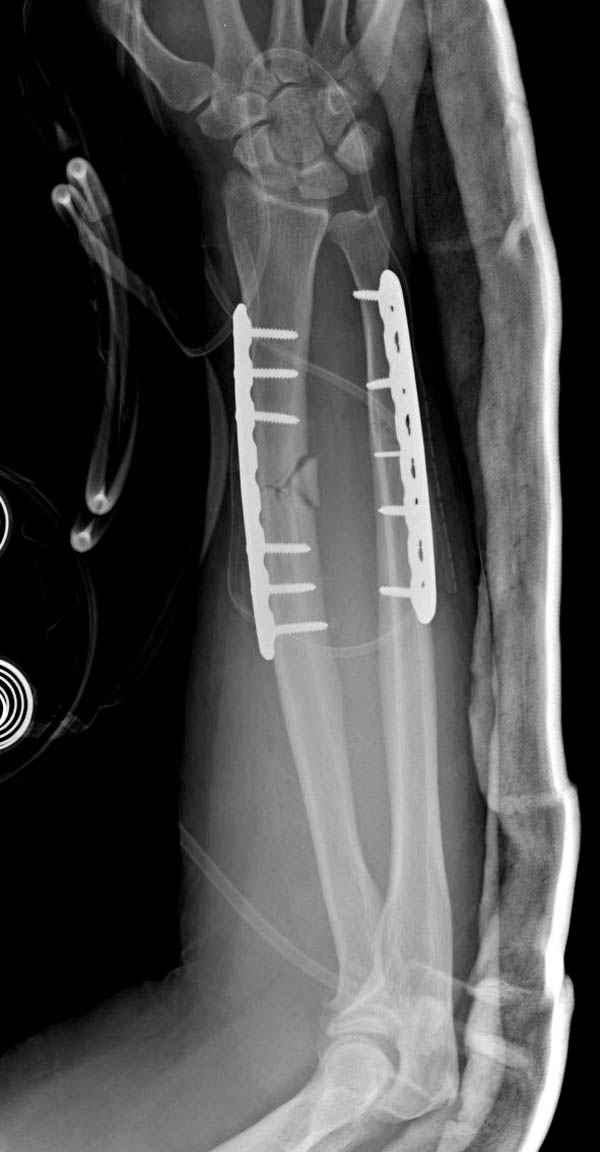

Второй случай, для лечения перелома проксимального

плеча применили пластину "Hand Innovation"

http://www.handinnovations.com/pdf/S3_technique.pdf

Пластина имеет преимущества перед другими "Locking

Implants", потому что пластину можно уложить намного ниже чем другие пластины и имеется возможности проведения шурупов под 130 градусным углом, таким образом можно уменьшить операционный разрез в проксимальной части.

Прооперирован вчера на 13 день после поступления.

Больному 41 и из-за гемодинамической нестабильности в течение первых 7 дней был в реанимации под интубационной седацией.

Кроме перелома плеча у больного старый дистракционный перелом T12-L1 оперированный когда-то и кем-то, открытый перелом костей предплечья, который был прооперирован в ночь поступления, после I&D (хирургической обработки). Из-за разрыва селезенки при поступлении травма хирургами произведено удаление.

Дополнительно имеется перелом ацетабулума: задняя

колонна с полупоперечным переломом, и переломы костей лица.

На седьмой день зафиксирован перелом ацетабулума через задний доступ. Перед операцией для профилактики DVT, IVC фильтер, также получает Lovenox.

Извиняюсь за качества снимков, обычный больной в 300 фунтов, портативным ренген аппаратом не пробить.